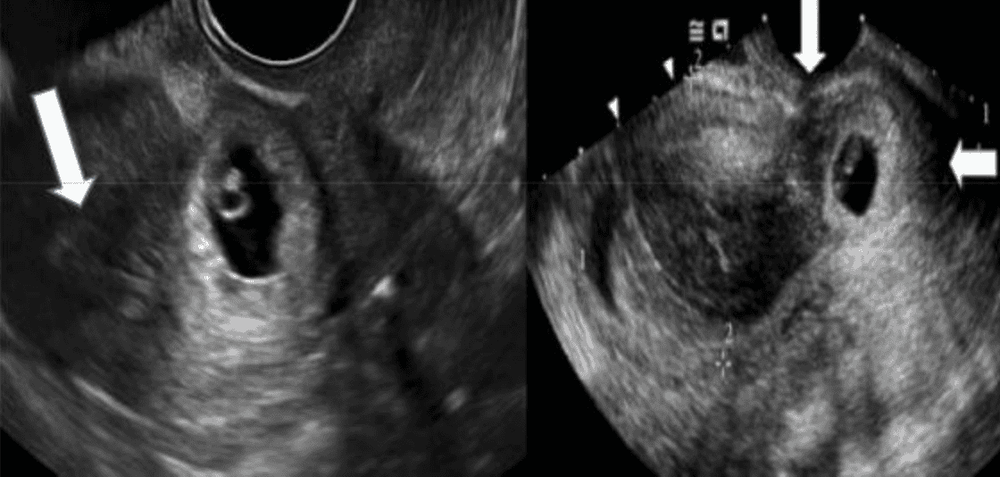

Ngoài các dấu hiệu trên, bạn có thể xác định xem mình có bị thai bám ở sẹo mổ cũ hay không bằng cách siêu âm âm đạo kết hợp với doppler, siêu âm 3D hoặc MRI không thường quy đối với những trường hợp khó chẩn đoán.